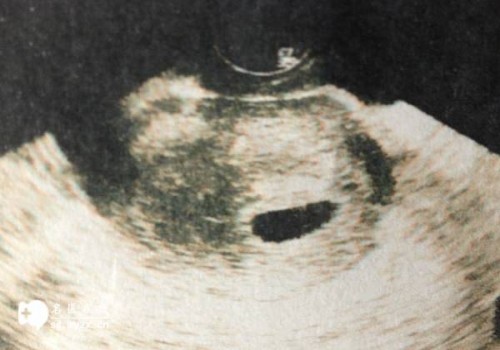

心脏造影检查是一种诊断非常重要的检查手段,它能够发现心脏结构和功能的异常。心脏造影检查可以帮助医生诊断心脏疾病,如心肌病,冠状动脉粥样硬化症,心肌梗死,心室纤颤等。

心脏造影检查是一种重要的检查手段,能够对心脏疾病进行诊断,发现心脏结构和功能异常。检查时间为1-2小时,在准备过程中,患者需要完成一些简单的准备工作,并进行一些必要的检查,然后在X线机或MRI机上进行检查。心脏造影检查不仅能发现心脏疾病,还可以检查心脏的功能和周围结构。